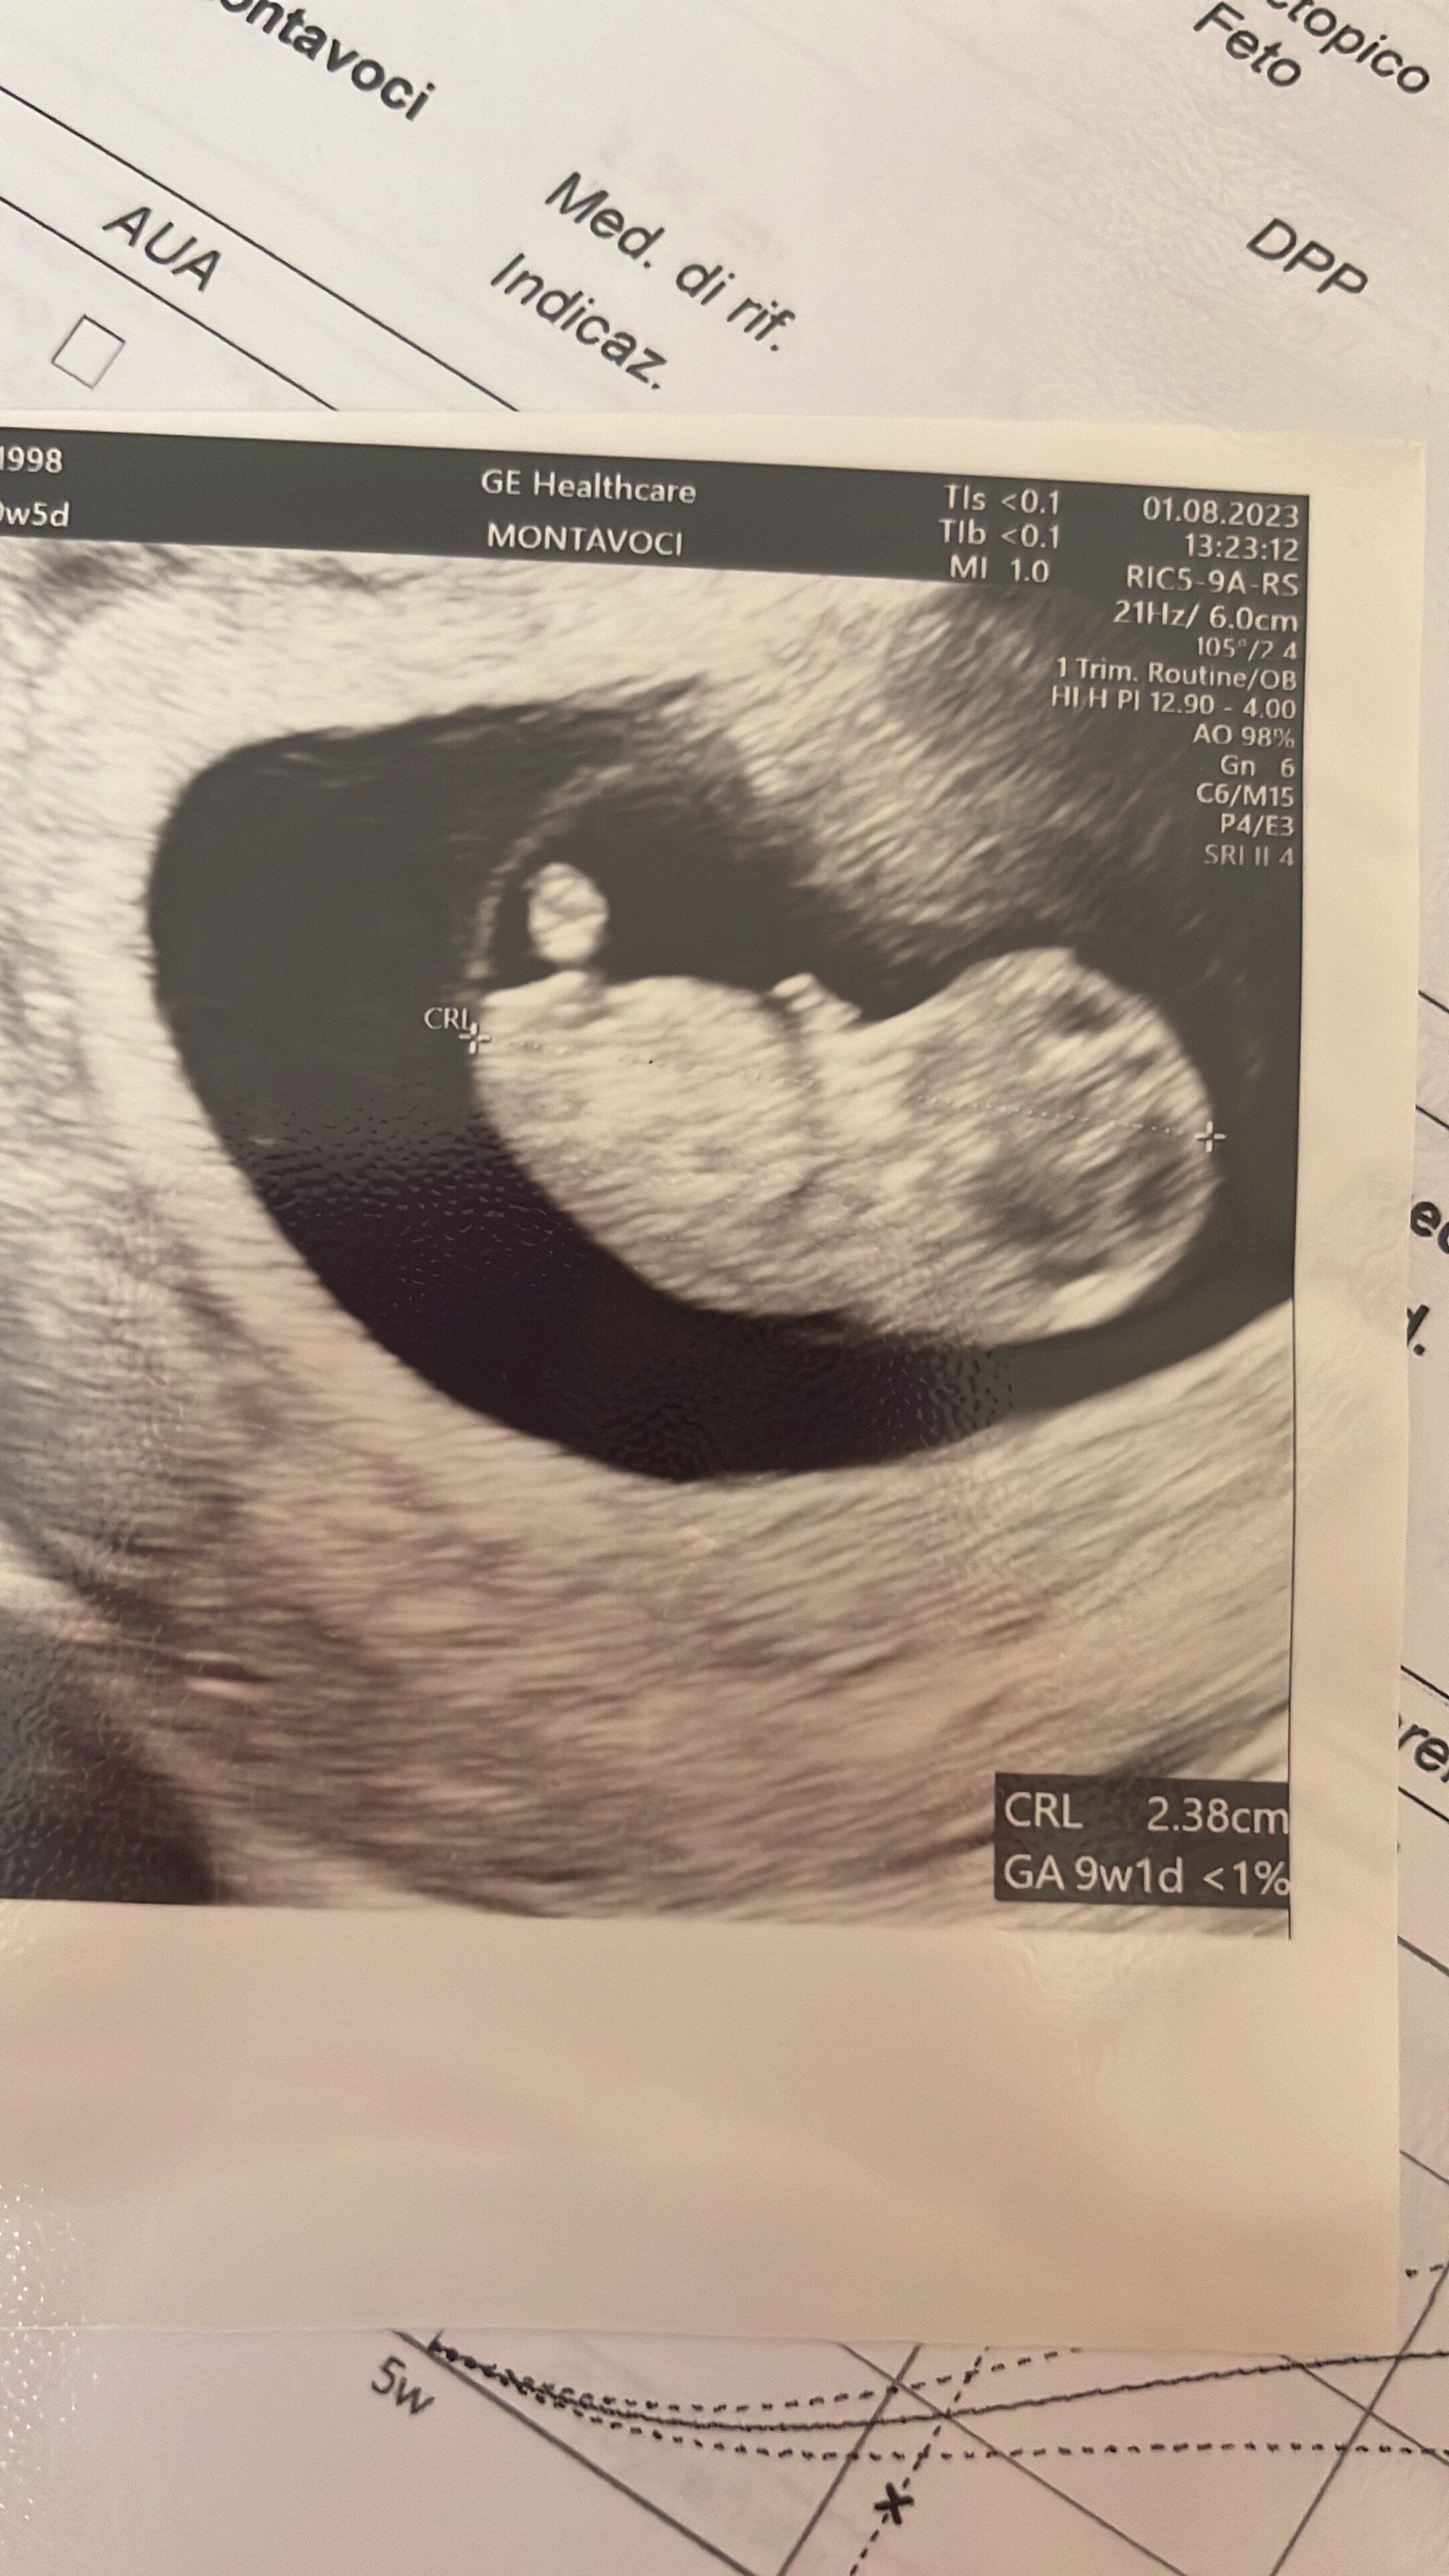

ale diabeł tkwi w szczegółach - najpierw robi się biopsję kosmówki, żeby sprawdzić czy dziecko nie jest zakażone. Następnie można to leczenie prewencyjne włączyć. Leczyć już zakażone dziecko w okresie prenatalnym też można tzn zminimalizować skutki działania wirusa, ale to ma sens w drugim, trzecim trymestrze wg informacji jakie zebrałam. Bo jak wiadomo w pierwszym to już "nie ma czego zbierać"

może w DE znajdą jakieś rozwiązanie dla mnie... Spróbuję załatwić jakaś wizytę koło 20 sierpnia, najlepiej byłoby mi dowiedzieć się czym prędzej czy przekazałam chorobę czy nie. Jeśli tak to wiadomo... Lepiej nie ryzykować z czekaniem i złudną nadzieją, żeby się nie skończyło bardziej traumatycznymi przeżyciami